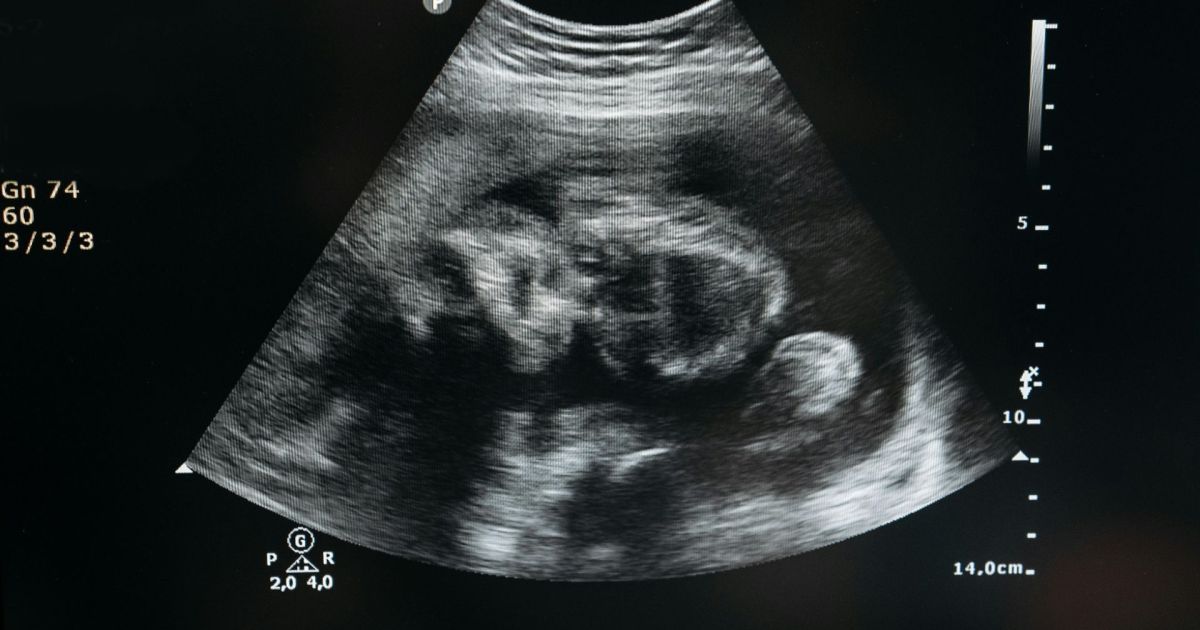

A 1ª Câmara Criminal do Tribunal de Justiça do Rio Grande do Sul (TJRS) decidiu, por maioria, cancelar o júri popular de uma mulher acusada de aborto provocado em Porto Alegre. A decisão veio após ausência de provas concretas de autoria e técnicas que comprovassem a expulsão fetal.

Segundo os autos, não houve exame pericial que demonstrasse a realização de “manobras abortivas”.